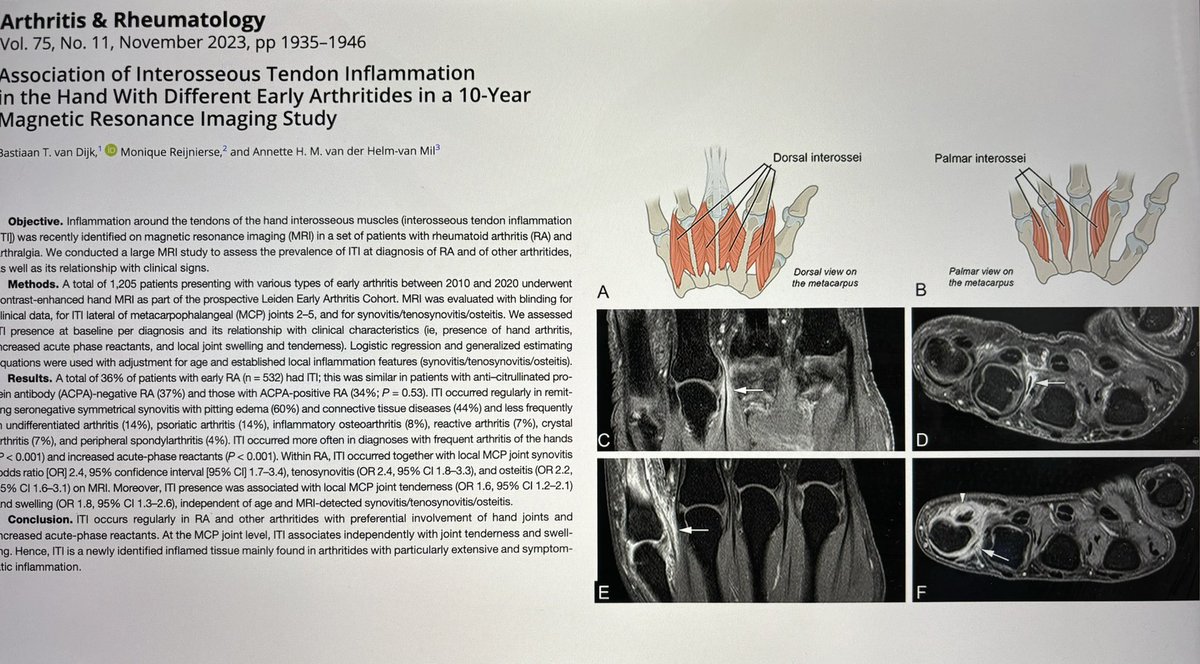

Encantado de participar con los Dres Benavent (H Bellvitge) y Corominas (H SPau) en la Mesa de Imagen del #SimposioAR24 Soc.Esp.Reumatología